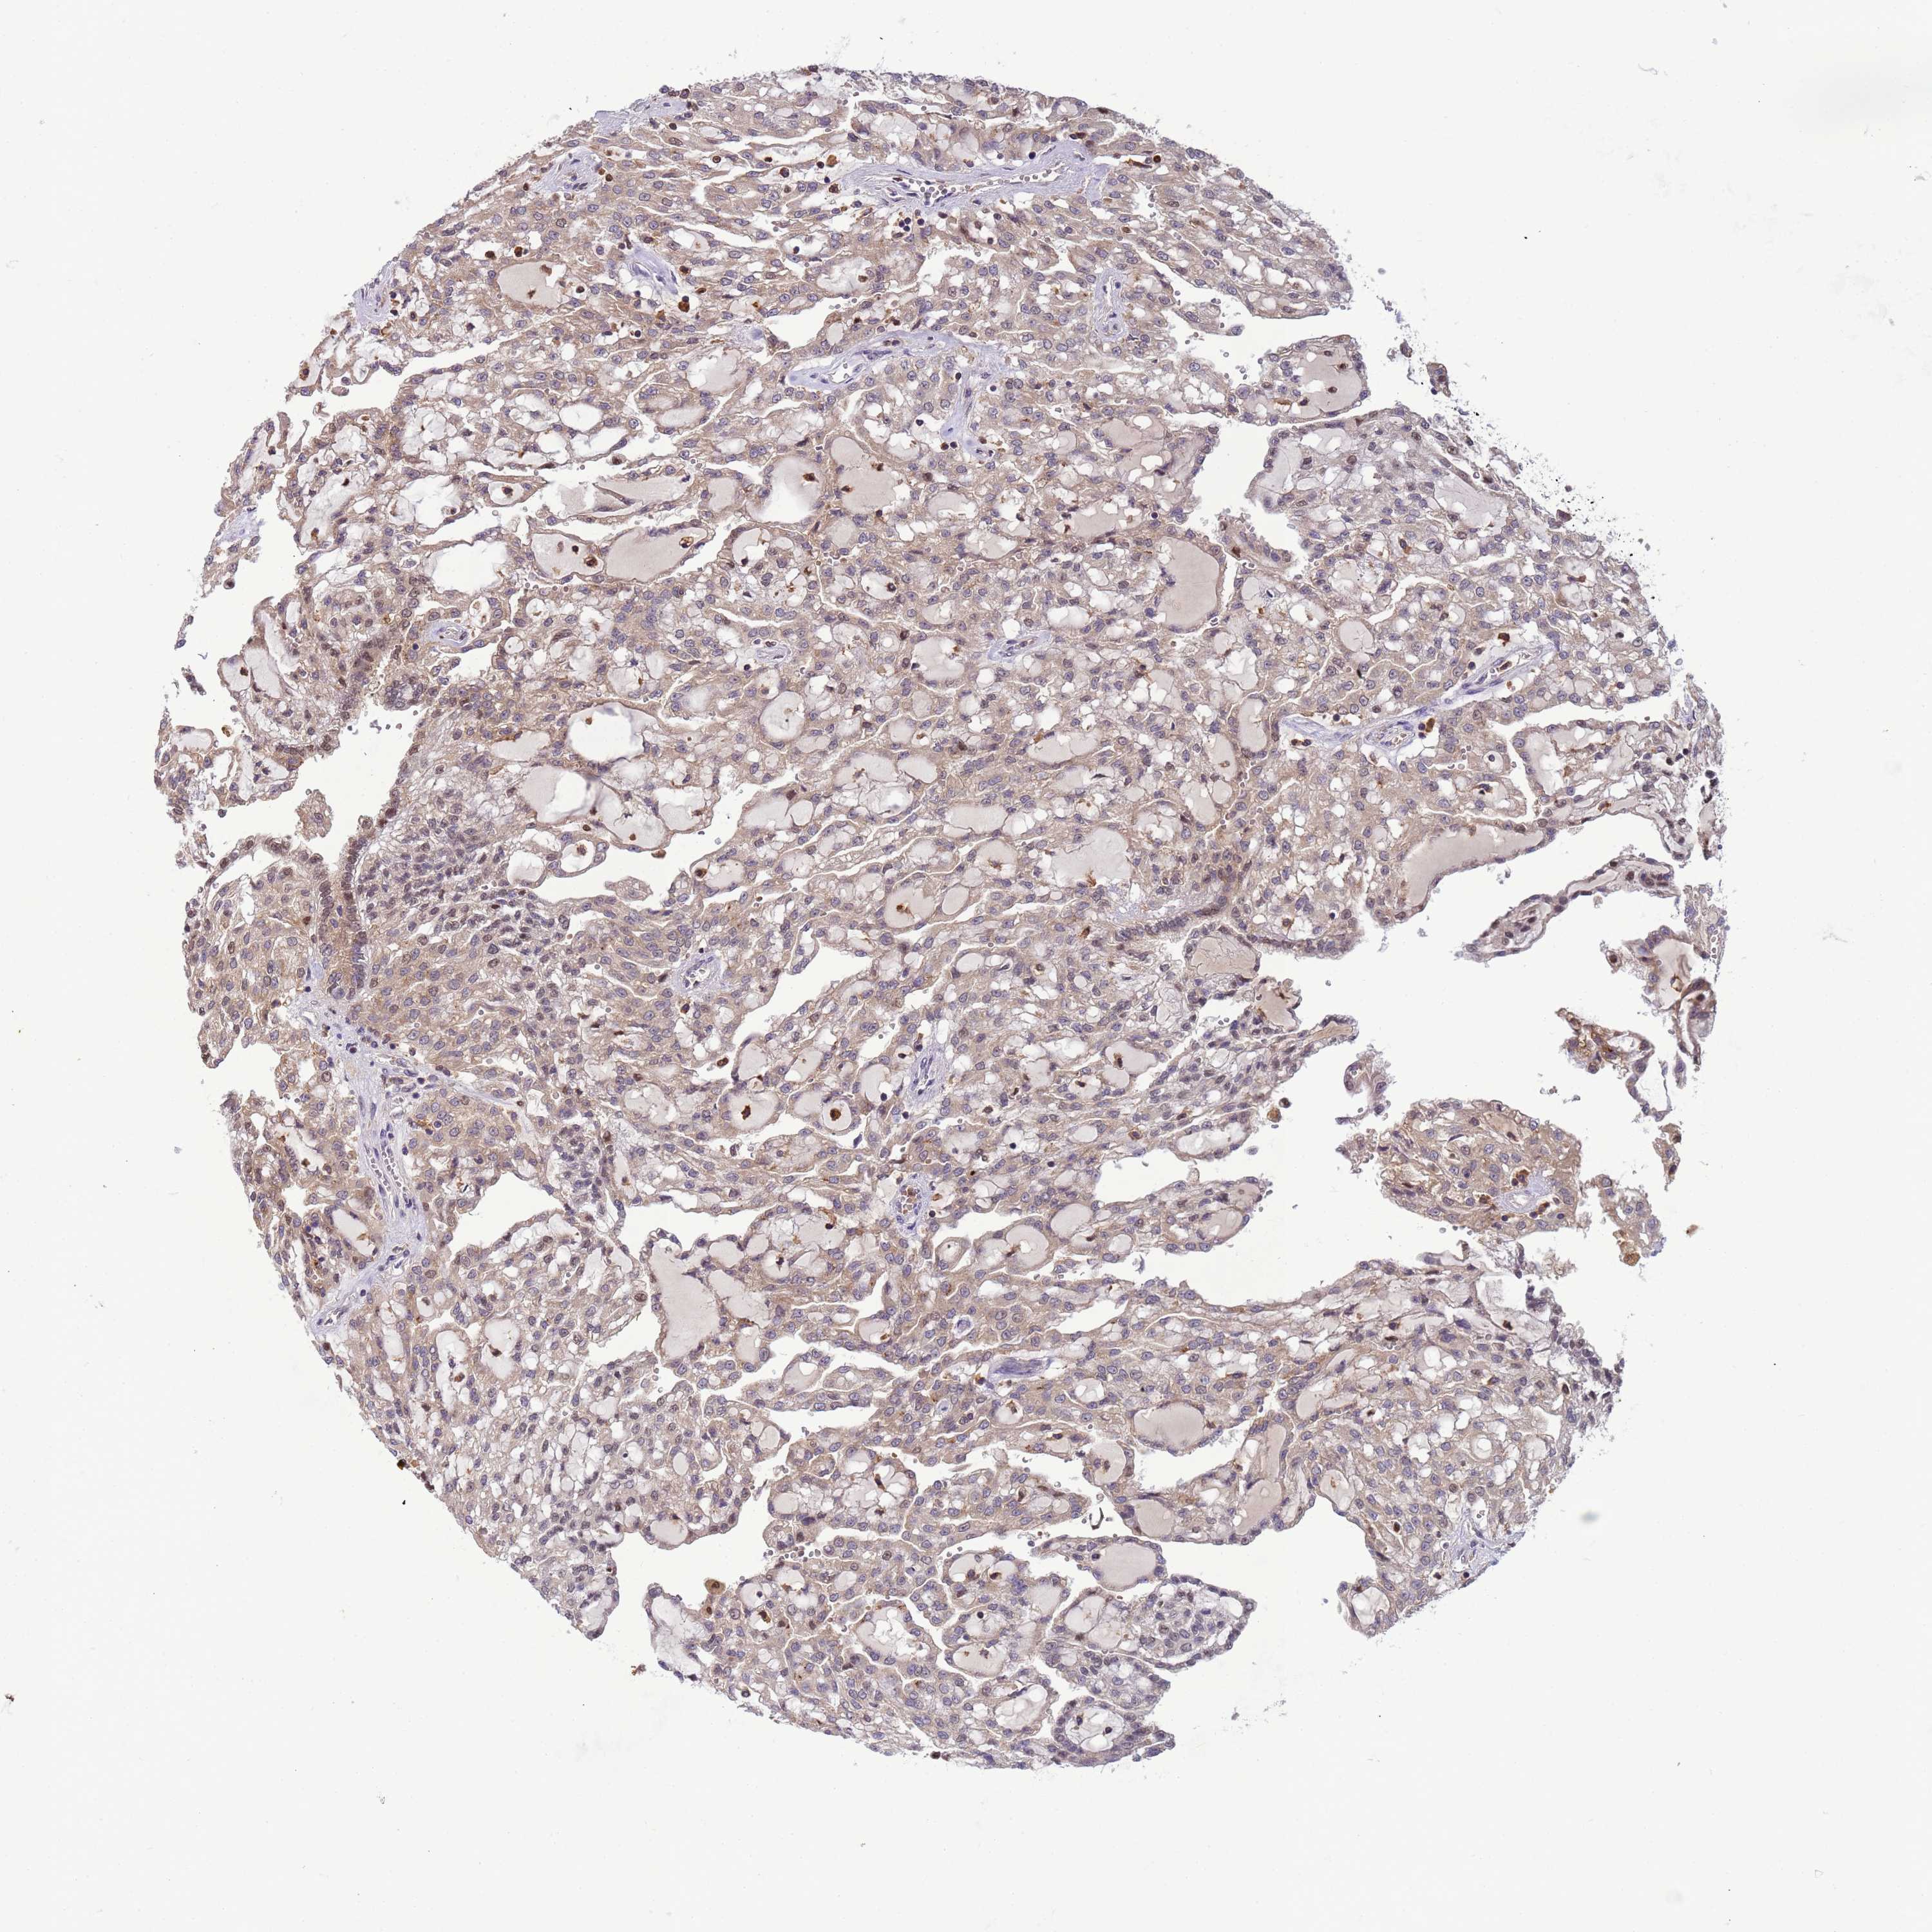

KIDNEY RENAL PAPILLARY CELL CARCINOMA (TCGA) - Interactive survival scatter ploti

The Survival Scatter plot shows the clinical status (i.e. dead or alive) for all individuals in the patient cohort, based on the same data that underlies the corresponding Kaplan-Meier plots. Patients that are alive at last time for follow-up are shown in blue and patients who have died during the study are shown in red.

& Survival analysisi

Kaplan-Meier plots summarize results from analysis of correlation between mRNA expression level and patient survival. Patients were divided based on level of expression into one of the two groups "low" (under cut off) or "high" (over cut off). X-axis shows time for survival (years) and y-axis shows the probability of survival, where 1.0 corresponds to 100 percent.

CD53 is not prognostic in Kidney Renal Papillary Cell Carcinoma (TCGA)